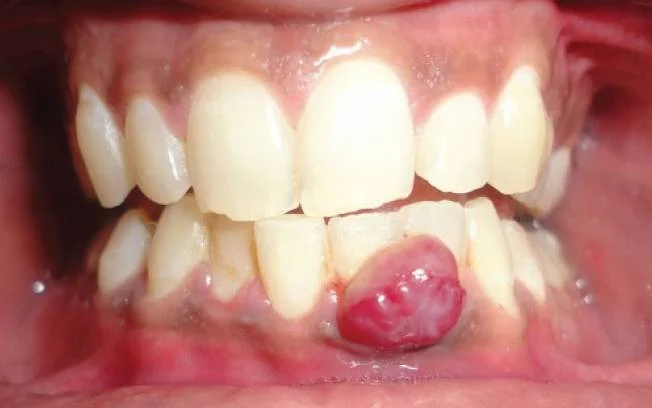

• Ретенционная. Образование появляется при смене молочных зубов постоянными. Признаком служит отек. Внутри него содержится кровь. Выглядит синюшно. Чаще возникает при медленном прорезывании.